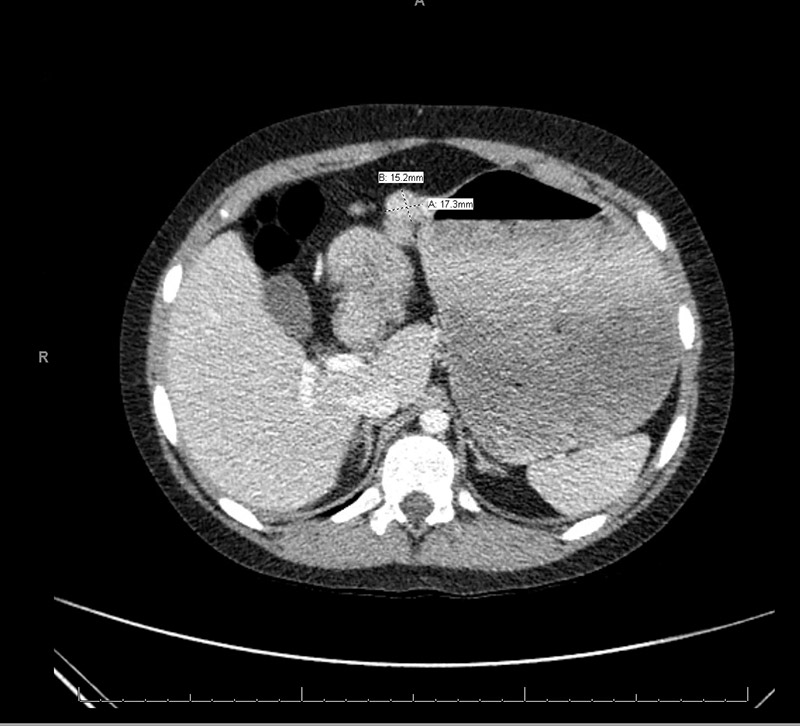

The polyp was non-obstructing and not actively bleeding; biopsies were taken of this polyp. Histologically the biopsy specimen demonstrated a proliferation of uniform mixed epithelioid and spindle-epithelioid cells amongst antral-type mucosa (Figures 2, 3). No significant pleomorphism or mitotic figures were identified. Immunohistochemical stains for DOG1 and c-Kit (CD117) were positive (Figures 4 and 5, respectively). A subsequent wedge resection of the stomach to include the lesions was performed and confirmed the original biopsy diagnosis (Figure 6). Molecular testing for c-Kit and PDGFRA were performed and were negative.